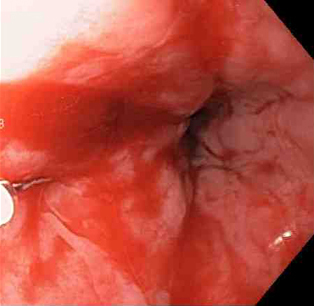

Actively bleeding tear appears as a red longitudinal defect with normal surrounding mucosa

From the collection of Juan Carlos Munoz, MD, University of Florida